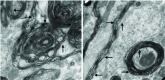

The myelinated nerves of mouse brain from the test group at 104 days post challenge. The plasma membrane had dissolved and spread out like mud (rightward arrow). In addition, there were bubbly structures (leftward arrow). Degenerative changes at the border between two myelin sheaths were more obvious (rightward arrow) and adjacent mitochondria are also damaged (downward arrow)

The myelinated nerves of mouse brain from the test group at 111 days post challenge. The rightward arrow points to the bubbly structures, the upward arrow points suspicious pathogenic fibres, and the downward arrows point to the polymerised bubble with polymeric particles